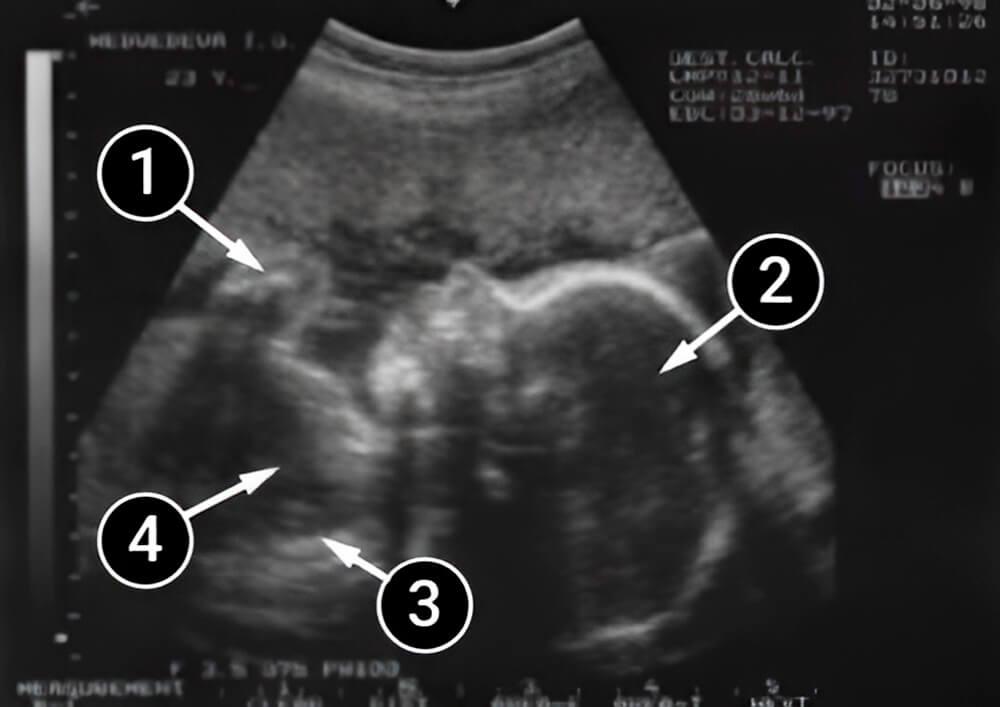

Lo que podemos ver en un ultrasonido

La imagen muestra la cabeza del bebé. También podemos ver su nariz, oreja y mandíbulas superior e inferior. Los arcos blancos que se ven en la cabeza son los huesos frontal y occipital. Los brazos están doblados a la altura de los codos y llevados hacia el pecho. Abajo se puede ver la columna, que parece una franja blanca. El área oscura en el pecho es el corazón.